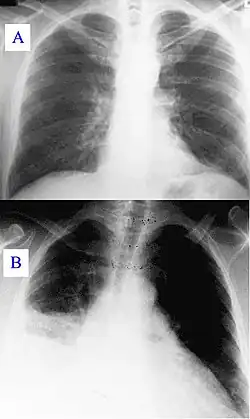

Signes radiologiques

Pneumopathie atypique

Échocardiographie

La fièvre Q peut provoquer une endocardite (infection des valves du cœur) chez les patients présentant une valvulopathie. Le diagnostic est fait par échocardiographie.